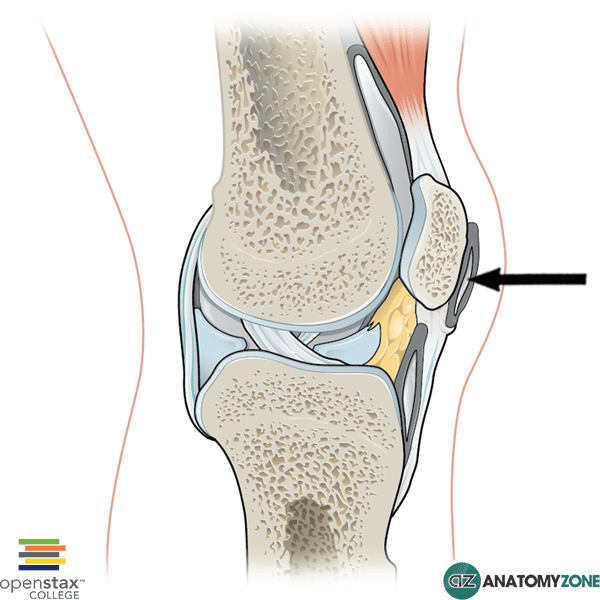

What is prepatellar bursa?

Prepatellar bursa is located at the top of the knee over the kneecap. Bursitis of the prepatellar bursa is sometimes called carpet layer’s knee, housemaid’s knee or roofer’s knee. It can be caused by a direct blow to the knee or from being in a prolonged kneeling position.

Where is the prepatellar bursa located?

Prepatellar bursa is located at the top of the knee over the kneecap. Bursitis of the prepatellar bursa is sometimes called carpet layer’s knee, housemaid’s knee or roofer’s knee. It can be caused by a direct blow to the knee or from being in a prolonged kneeling position.

A bursa is a fluid filled sack that serves to reduce friction between tendons, and between tendons and bone. The four major bursae of the knee are: Suprapatellar bursa is located between the distal femur (leg bone) and the quadriceps tendon. It permits free movement of the quadriceps tendon over the distal femur.

What is the bursa of the roofer's knee called?

Bursitis of the prepatellar bursa is sometimes called carpet layer’s knee, housemaid’s knee or roofer’s knee. It can be caused by a direct blow to the knee or from being in a prolonged kneeling position. Infrapatellar bursa is located below the kneecap, under the large patella tendon.